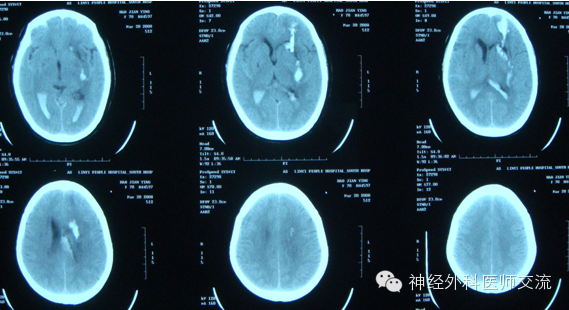

再来个延迟手术病例,这个病人开始不需要做,但是年轻人,反应重

一、 壳核出血

壳核出血占高血压脑出血的50%以上,积极完善地救治壳核出血对于降低脑出血的病死率,提高患者的生活质量具有重要意义。